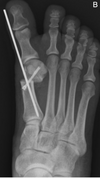

• Anatomia da superfície plantar da cabeça do 1° metatarso:

A